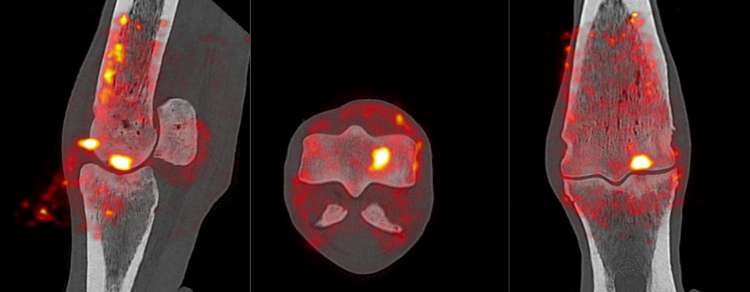

PET imaging is a form of nuclear imaging where a small amount of nuclear isotope is injected into the horse, which is then picked up by the scanner. Nuclear imaging has drawn criticism from both owners and trainers for its perceived health impacts on the horse, but the reality is that the nuclear isotopes most commonly used in PET and similar imaging procedures are extremely low risk and are almost completely removed from the body within 24 hours.

An example of PET scan images

Racing Victoria trialled the technology in the spring of 2024 and were happy enough with the results to make PET imaging more available in 2025.